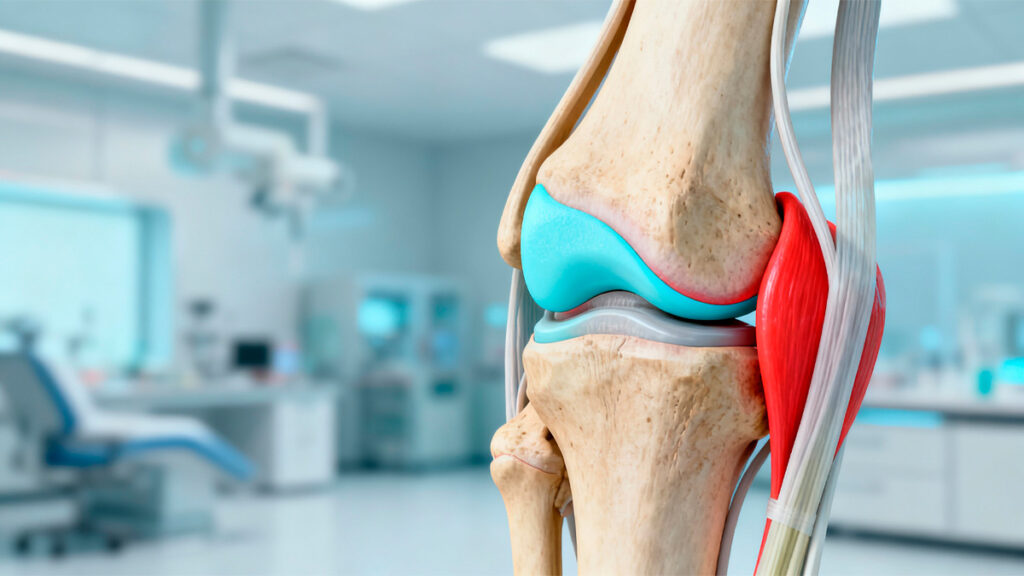

Quando se trata de dores no joelho, lesões como rompimento de ligamentos ou desgaste por artrose, é essencial contar com um médico que realmente entenda da complexidade dessa articulação. O ortopedista especialista em joelho é o profissional mais indicado para diagnosticar, tratar e acompanhar essas condições de forma precisa e eficiente.

O ortopedista é o médico responsável por tratar problemas nos ossos, músculos, articulações, ligamentos e tendões. Mas, dentro dessa especialidade, alguns profissionais escolhem se aprofundar ainda mais — como é o caso do especialista em joelho. Esse médico passa por uma formação complementar, com residência médica, cursos avançados e participação em sociedades médicas voltadas exclusivamente ao joelho.

O joelho é uma das articulações mais exigidas do corpo humano. Ele sustenta nosso peso, permite movimentos como caminhar, correr, agachar e pular — e por isso está mais propenso a lesões e desgaste.

O ortopedista geral tem conhecimento amplo sobre todo o sistema musculoesquelético, o que é excelente em situações mais simples. Já o especialista em joelho mergulha nos detalhes dessa articulação, acompanha os avanços mais recentes da medicina esportiva e cirurgias do joelho, e realiza procedimentos com maior frequência — o que resulta em maior experiência prática.